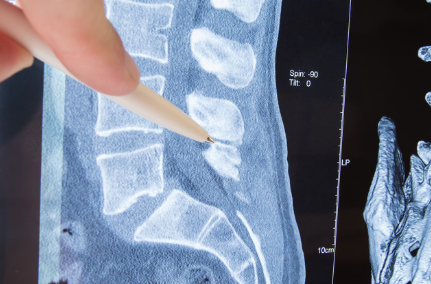

一般情况下,如果是外伤引起的马尾神经受损,意外、车祸、高处摔伤等等这类因素,神经恢复是很难的,需要一个很长的阶段,这是急不来的病。能否恢复取决于治疗是在什么阶段,如果早期正确治疗,神经恢复的概率是很大的,但也无法保证能够完全恢复,而且在马尾神经损伤患者中,只有极少数会在初期有效治疗,甚至大多数患者在患病之时,根本不知道是马尾神经损伤或者从来没有听说过这个病。

原因是大部分患者有腰椎病史,马尾神经综合征在腰椎间盘突出症患者中属于较为严重的并发症,虽然通过保守治疗可以解决大部分腰椎间盘突出症的问题,但是社会发展伴随工作的压力,让越来越多的人选择短暂忽视身体的一些问题,导致越来越多的人患上马尾神经损伤,也越来越趋于年轻化。病人一旦发展到马尾神经受损,一般都建议立马手术,术后康复锻炼结合药物促进恢复。完全性恢复的患者在比例上占少数,大多数病人通常都是不完全恢复的。

马尾神经损伤大部分属于3度范畴,或者是马尾神经损伤程度导致并发症的出现,马尾神经也要区分于其他的神经。马尾神经一般是不容易受损的,但是一旦受损,即便是轻微的压迫症马上接踵而来。再加上手术不确定因素太多,很可能造成二次损伤,加重病情也不一定。